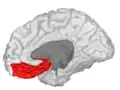

![]() Approximate location of the OFC shown on a sagittal MRI | |